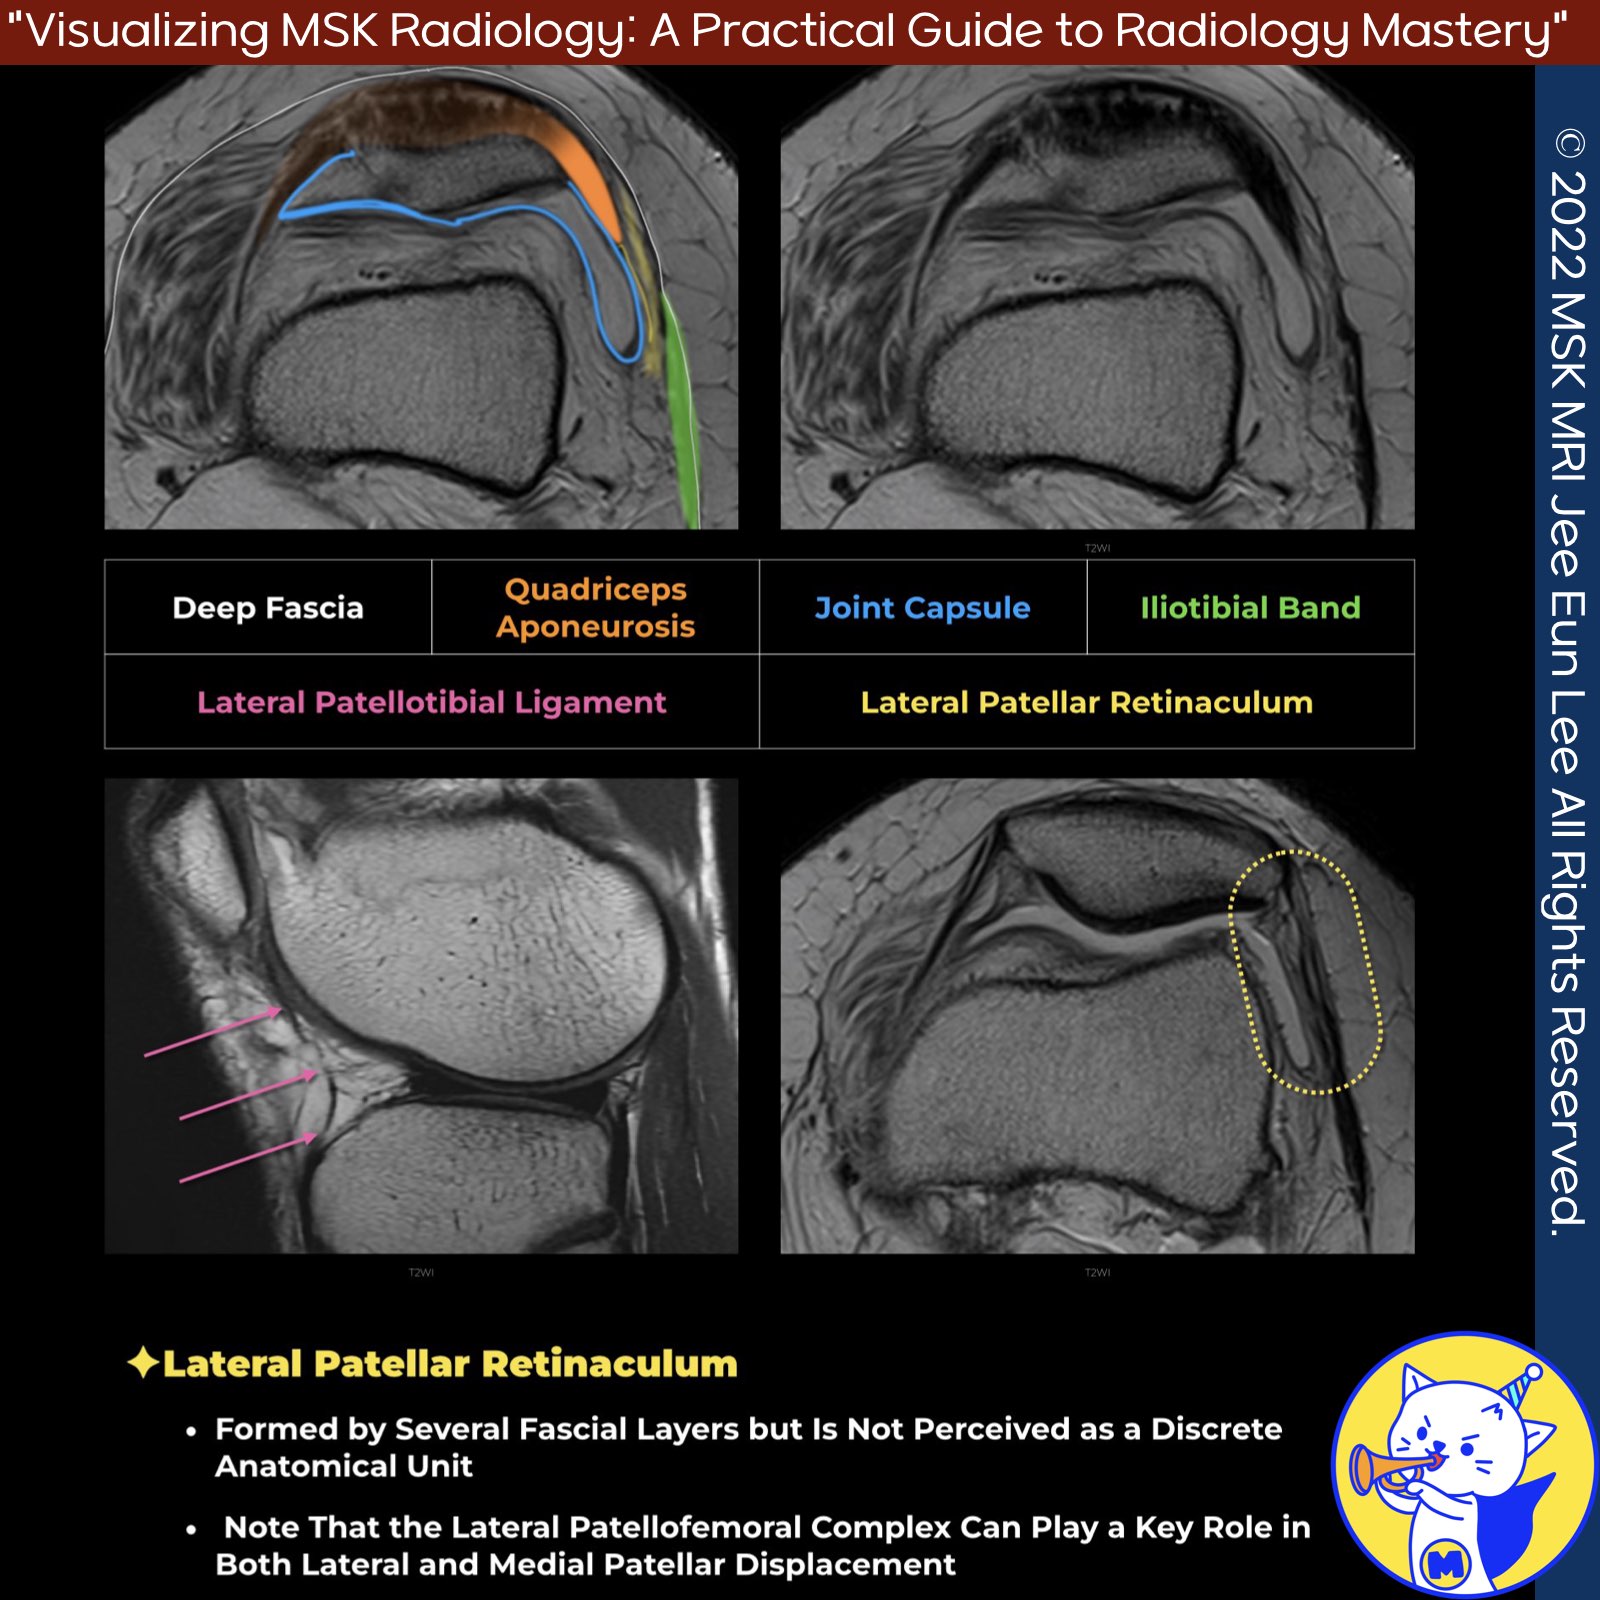

📌 The Lateral Patellofemoral Complex

- The primary component of the lateral patellofemoral complex is the lateral patellofemoral ligament, which extends from the lateral patella and adjacent patellar tendon to the femur, specifically distal-anterior to the lateral femoral epicondyle.

- Lateral patellomeniscal ligament: spanning from the inferolateral patella to the lateral meniscus anterior horn.

- Lateral patellotibial ligament: extending from the inferolateral patella to the adjacent tibia near the Gerdy tubercle.

- The lateral patellofemoral complex plays a crucial role in both lateral and medial patellar displacement.

- Due to concerns about iatrogenic medial patellar instability, many surgeons now perform a controlled retinacular "lengthening" procedure instead of a traditional lateral "release" procedure.

- The lateral retinacular complex is more robust and less frequently injured compared to the medial retinacular complex. It consists of three layers:

- The deep fascia forming the superficial layer

- Contributions from the vastus lateralis obliquus, quadriceps aponeurosis, and iliotibial band forming the intermediate layer (including the lateral patellofemoral ligament)

- The joint capsule accounting for the deep layer